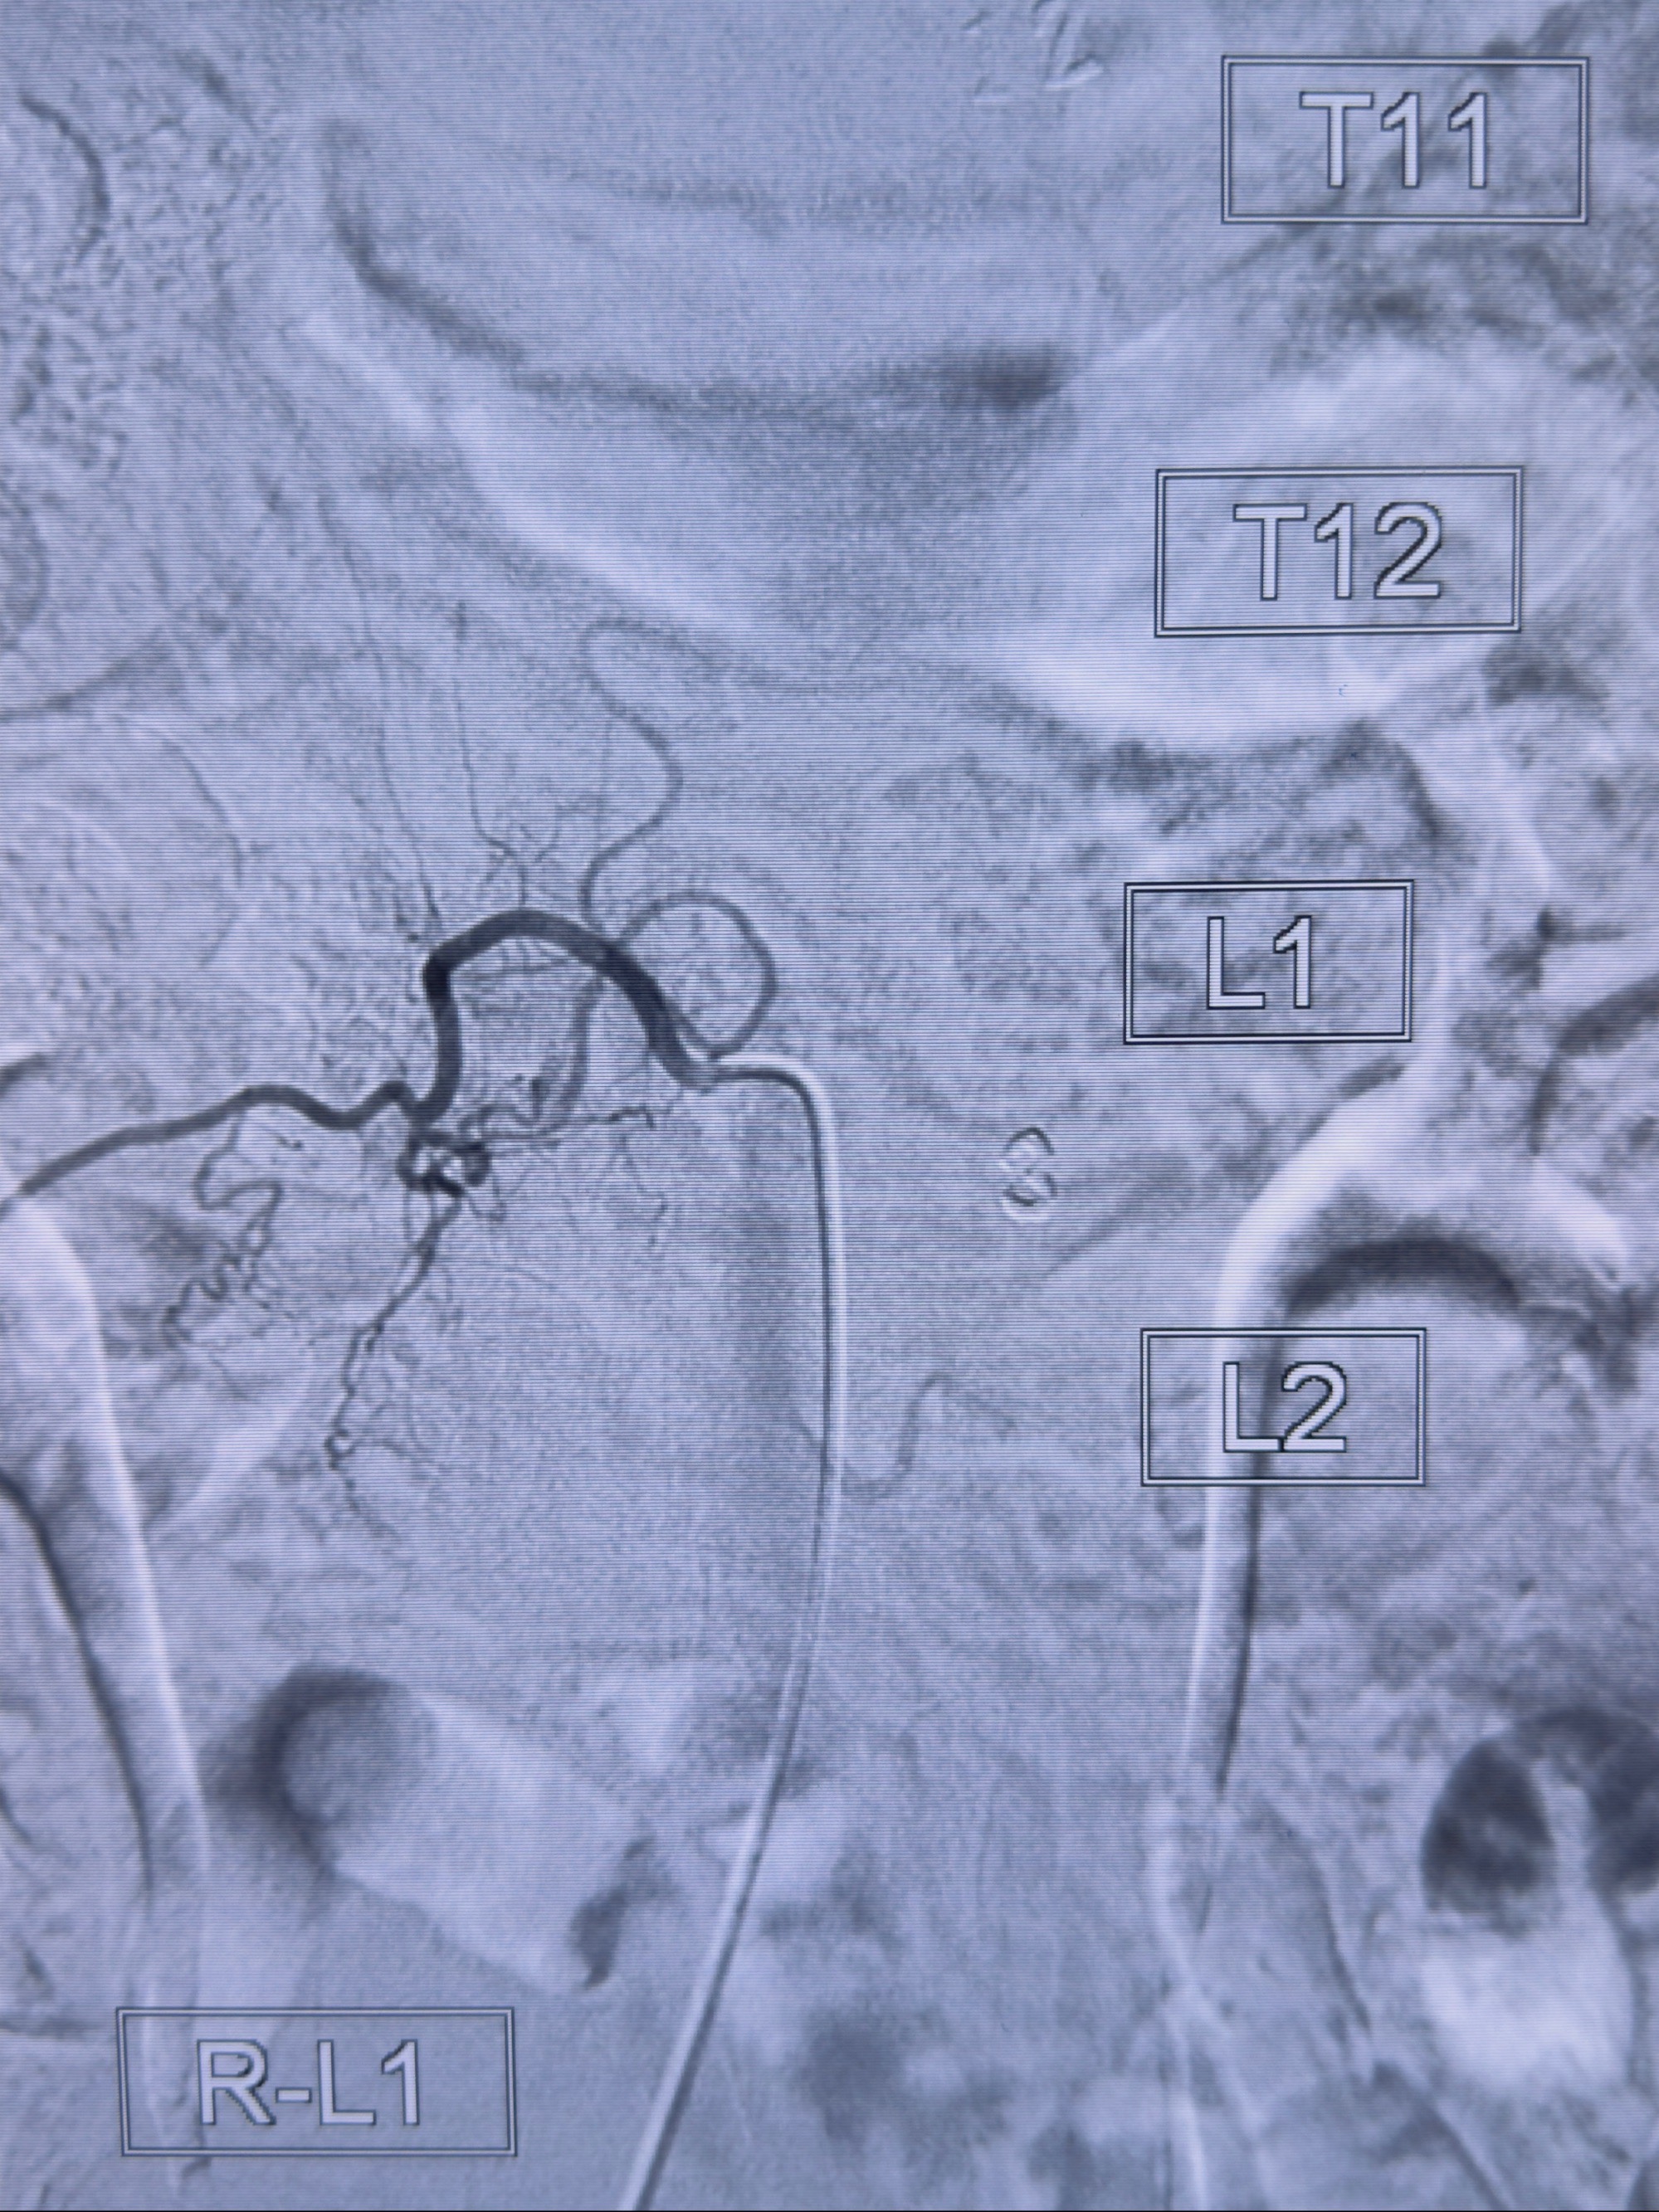

2023-10-13DSA:右侧L1水平硬脊膜动静脉瘘,供血动脉为右侧L1,附近动脉未见明确吻合供血,供血动脉处可见脊髓前动脉发出

1.建议外科手术,已行美兰定位c